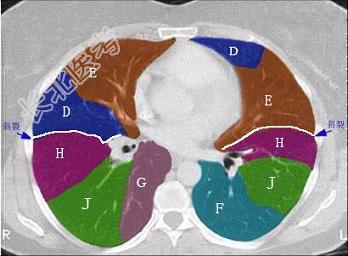

- 单项选择题结合肺段模式(见图),选出右肺下叶的组成 ( )

A、F

B、F+G

C、F+G+H

D、F+G+H+I

E、F+G+H+I+J